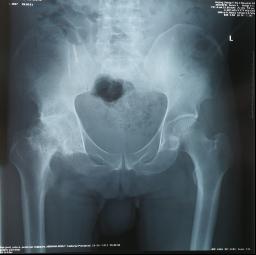

手术前 手术后